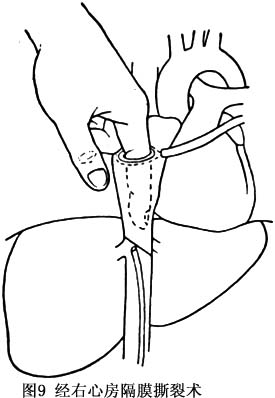

②經右心房隔膜撕裂術:方法是經右前第4肋外胸切口或經胸骨切口進入胸腔,於右膈神經前縱行切開心包。在右心耳部位作荷包縫線,剪開心耳,以示指探查右心房及下腔靜脈,對於隔膜位置較高的病例,示指可捫及隔膜,以示指強行撕裂(圖9)。對於厚型隔膜或有明顯下腔靜脈狹窄的病例,可經右心房或股靜脈放入帶囊導管行擴張術。隔膜遠端血栓形成者不能採用本法,以防肺栓塞。行隔膜撕裂術後,下腔靜脈內仍有破碎不規則的隔膜殘留,也不能去除同時存在的狹窄或受壓情況,易形成下腔靜脈再阻塞。